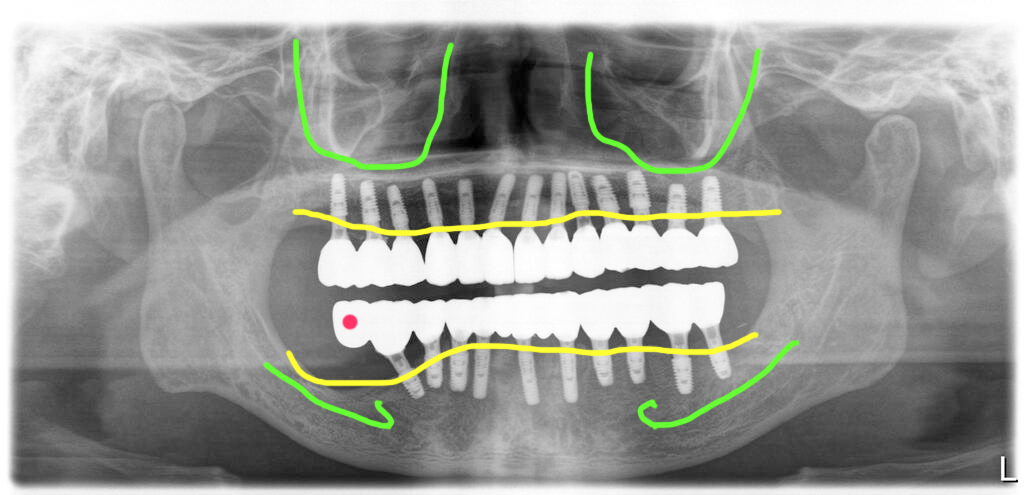

4회 내원 치료기간 3개월 전체임플란트 치료완료

신경과 가까운 부위에 임플란트를 식립하지 못한 것을 제외하고는 환자의 뼈상태는 양호한 편이었습니다.

수술시 초기고정이 좋았기 때문에 수술당일 임시치아도 해 드렸고, 수술 후 3개월만에 최종보철을 완성해서 세팅해 드렸습니다.

치주염으로 전체임플란트 치료를 받으시는 경우 치료후 관리시 환자가 구강위생관리를 잘 하는지 확인이 꼭 필요합니다. 습관을 바꾸는 것이 쉽지 않기 때문인데요. 그래서 정기검진을 꼭 잘 해 주어야 합니다.